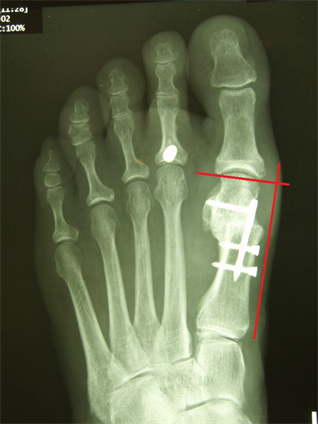

Figure 5. Patient Nr. 1. Correction of a pathological DMAA without loss of length. Distal fragment has only a point contact to the proximal bone partner. Additional Akin osteotomy and PIP arthrodesis and FDL tranfer on the 2nd toe.

Figure 6. Patient Nr. 1. After 6 months the bone healing is completed with no loss of correction. Immediate full weigh bearing was allowed.